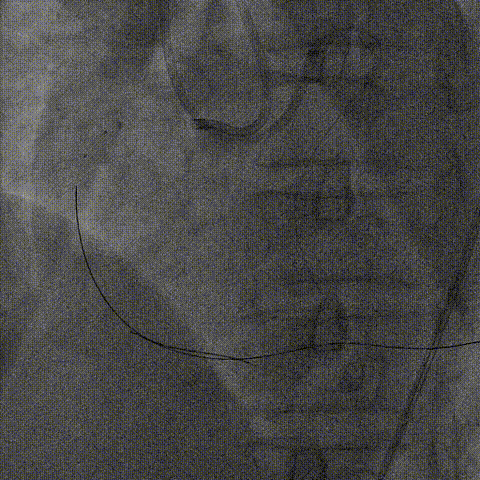

血管内超声:

导丝远端位于血管真腔,闭塞段部分内膜下走行,可见闭塞段钙化,符合术前评估结果。

支架植入:

根据血管内超声结果,在Telescope™支撑下序贯植入3.0mm、3.5mm、4.0mm支架3枚,4.0mm直径支架通过Telescope™延长管顺畅,无连接部剐蹭情况。

6F Telescope 支撑下序贯植入Ø3.0 3.5 4.0mm支架,通过性优异